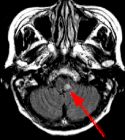

Fig. 1 Fig. 2 Fig. 3 Fig. 4

MRI Findings: In the supratentorial regions, some atrophy and chronic small vessel deep white matter ischemic changes were observed (Fig. 1) but no acute lesion or infarct was observed on MR diffusion. In the posterior fossa, however, a subtle small 1 cm hyperintensity can be seen in the left side of medulla on T2 weighted (Fig. 2) and FLAIR images (Fig. 3). This can be seen with an infarct, but its age would remain indeterminate. The MR diffusion image (Fig. 4) shows hyperintensity in the same region consistent with an acute infarct (arrows) as opposed to chronic ischemic changes.